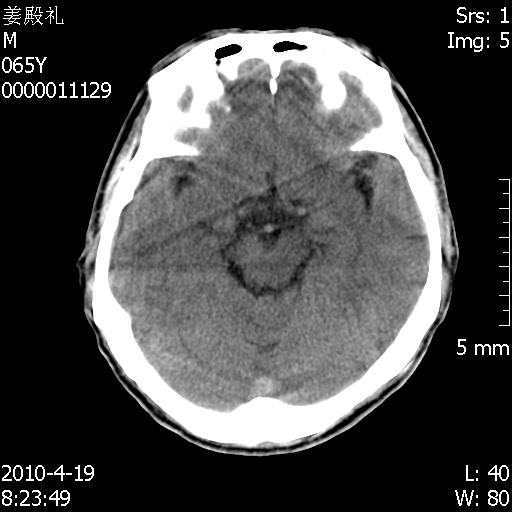

老年男性,突发左下肢无力1天,其余有价值的检查都没有。平扫ct值大约60hu,增强后ct值没什么改变,请大家讨论一下这个病例是什么?说明诊断理由。

左小脑、右大脑顶叶多发圆形高密度病灶,其周环状低密度影。考虑多发脑出血。隔期观察。

至于是出血还是微小钙化所致的高密度无法考证,三个都出血也不是一点都不可能,同一种组织学类型的肿瘤受到同一个外来的因素影响后会表现出相同的病理变化。说实在的,我本身支持转移瘤的,就是想不通为什么不强化?我认为单纯脑出血的边缘不会那么光滑,并且那也不是出血的常见部位,多发也不常见。

今天上班后发现病人前天复查(4月18日发病,19日初诊,22日复查),三个病灶均明显增大,边缘仍旧清楚,水肿加重,右侧脑室基本闭塞。

我想:如果是肿瘤出血的话,一般不会导致体积明显改变,水肿又进一步加重;如果是出血灶,那么现在应该正好是水肿加重的时候,还是比较符合,但是为什么边缘又是这样的特点?